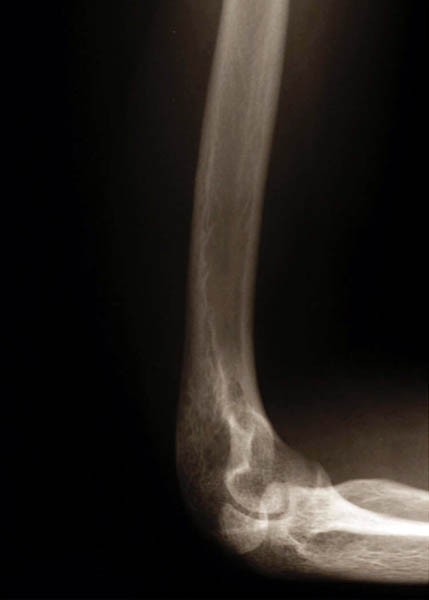

Wear and tear – Osteoarthritis of the elbow is actually very rare, as it is essentially a non- weight bearing joint, and unless there is a previous injury to the joint (for e.g. a fracture at the level of the elbow, especially if within the joint).

However, if there is other types of arthritis (e.g. Rheumatoid arthritis, Psoriatic arthritis) already affecting other joints, then the likelihood of elbow arthritis of the same type increases.